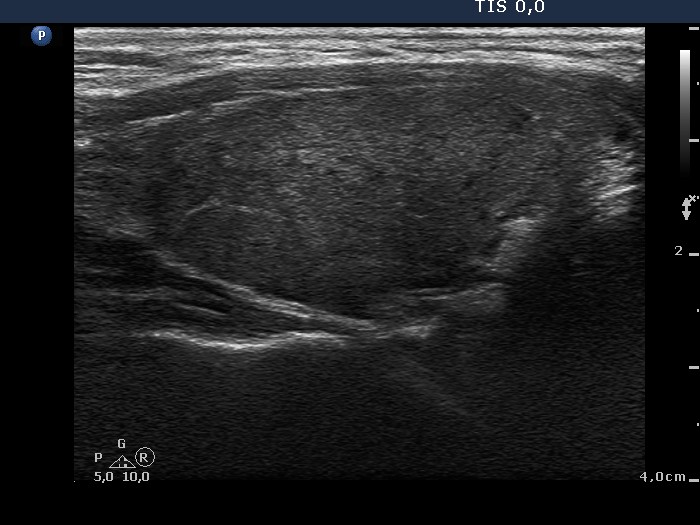

Chronic lymphocytic thyroiditis - Figure 1. Ultrasound patterns according to the degree of hypoechogenicity.

Diffuse hypoechogenicity is the most important sonographic sign of Hashimoto's thyroiditis. The degree of hypoechogenicity varies greatly, and correlates relatively well with aTPO level. We have to notice the hypoechogenicity in a euthyroid patient in order to consider the possibility of the underlying autoimmune thyroid disease and therefore to give the chance to recognize hypothyroidism later.

A minimally hypoechogenic thyroid.